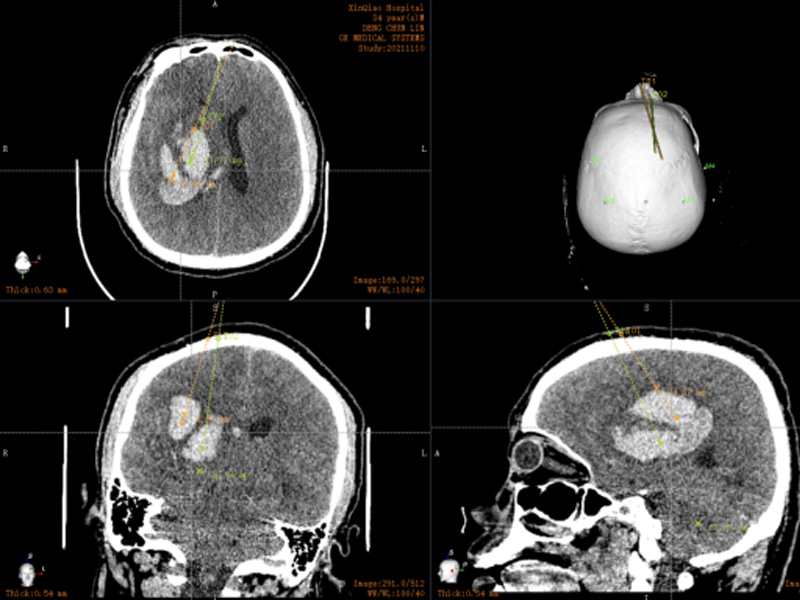

Cases 2